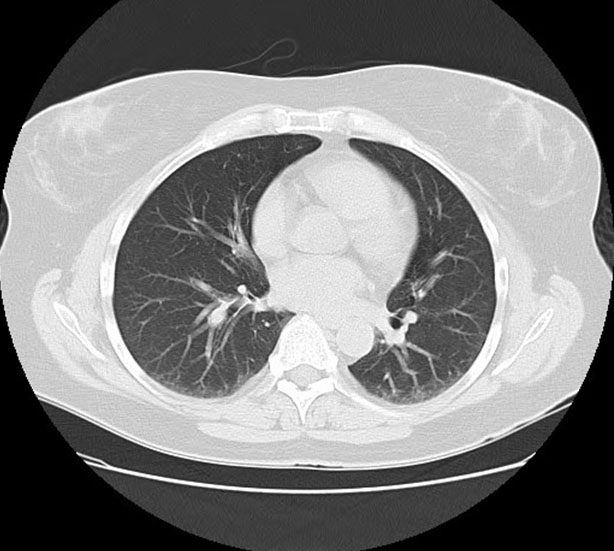

Radiologist: the chest CT without intravenous contrast (Figure 2) showed bilateral peripheral areas of consolidation and ground-glass opacities which persisted on the prone images. Septal thickening was present, primarily in the lung bases. Diffuse centrilobular nodules were noted as well. There was also apparent mediastinal adenopathy.

Figure 2: Chest CT without intravenous contrast prior to admission—bilateral peripheral areas of consolidation and ground-glass opacities with septal thickening primarily in the lung bases. Diffuse centrilobular nodules and apparent mediastinal adenopathy.

This differential was first considered by pulmonology when the patient was evaluated for chronic cough with CEP-like presentation: dyspnea, chills, fever, wheezing, and eosinophilia. Additionally, the patient’s eosinophilia initially did not improve with prednisone and her infiltrates did not improve with antibiotics. The patient’s chest X-ray also showed characteristic findings, which included multifocal, predominantly upper peripheral ill-defined infiltrates without definite peribronchial interstitial thickening. This differential was also suggested by radiology when a CT without contrast revealed findings that are highly suggestive of CEP: bilateral peripheral areas of consolidation and ground-glass opacities (Figure 2). On further workup, bronchoscopy revealed eosinophilia with an absence of infection, further supporting CEP as a possible diagnosis. With many overlapping features, the patient was referred to rheumatology, at which time ACNA was re-ordered. Although negative at admission, the patient’s c-ANCA came back positive 40 days after her hospitalization (Table 1). This pattern of late ANCA positivity made EGPA more likely, since ANCA is typically only positive in 40–60% of EGPA patients [16].

Sjögren’s syndrome was first considered after initial workup by pulmonology when labs revealed a positive RF and Sjögren SSA antibody (Table 1). Although SSA antibodies are not sufficient to make the diagnosis, SS was taken into consideration due to the patient’s respiratory symptoms mimicking that of pulmonary involvement in SS. Additionally, various features overlapped with regard to imaging. Such features include bronchiectasis, ground glass opacities, and consolidation (Figure 1 and Figure 2). Nevertheless, these pulmonary findings are nonspecific, and SS should not be diagnosed solely based on positive antibodies. With the patient lacking supportive features of ocular or oral dryness, SS is unlikely. If these characteristic symptoms develop, additional workup with Schirmer test or ultrasound may be indicated for further analysis.